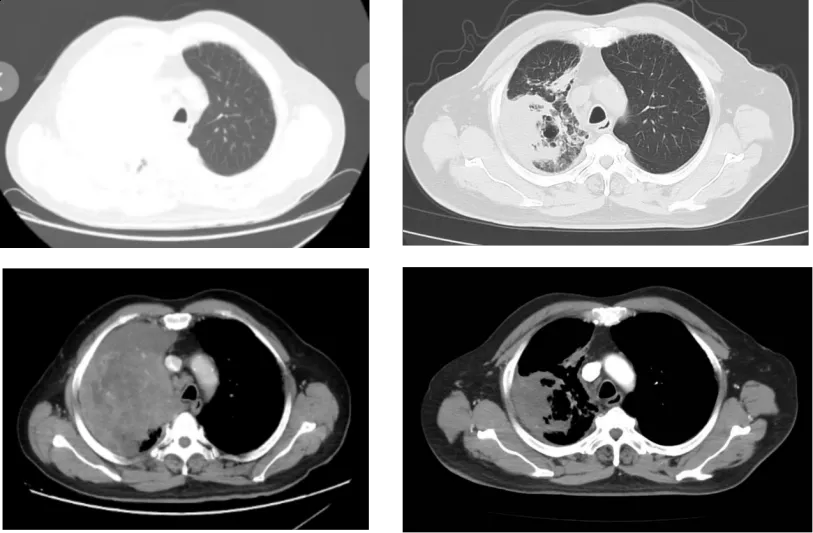

为精准救治患者,王海永主任团队迅速启动多学科评估,结合患者病情,建议其加入由王海永教授发起的针对该罕见亚型的专项临床试验——“艾帕洛利托沃瑞利单抗联合含铂双药化疗和盐酸安罗替尼治疗SMARCA4缺失的晚期或转移性非小细胞肺癌的单臂、II期探索性研究”,采用免疫+抗血管+化疗的“三联联合”治疗方案。2025年7月31日,郑先生开始接受规范治疗,方案为艾帕洛利托沃瑞利单抗350mg+培美曲塞700mg d1+卡铂400mg d1+安罗替尼10mg d1-14,每3周为一周期。完成两周期治疗后,肿瘤明显缩小,患者胸闷憋气等临床症状完全消失,生活质量显著提升。目前,郑先生仍在按计划随访治疗,持续从该联合疗法中获益。

治疗前 2周期治疗后